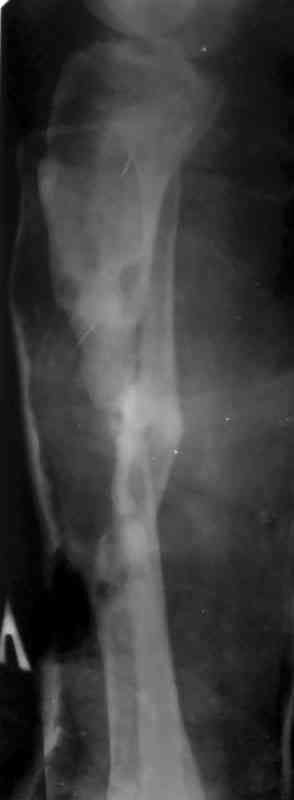

дефекта: за счет удлинения концов б\б кости или тибиализации м\б. На начальном этапе фиксация только в аппарате, в последствие для удержания достигнутого можно перейти на фиксацию интрамедуллярным штифтом (см. вложенные файлы)

Как дополнение высылаю снимки и фото конечности, чтобы Вы могли оценить состояние м/т, и течение заболевания.

Кстати на предоперационных снимках видно, что Ваш пациент имел Сегментарный перелом на границе верхней и средней трети большеберцовой кости и средней трети большеберцовой кости. Непонятно почему был удалён средний сегмент перелома.Почему в течении такого большого времени не предпринимались попытки для замещения деффекта.

Судя по месту расположения свища, наличия литического учаска в проксимальной части дистального фрагмента на последнем снимке, и, наличие в этом месте стержня Шанца на послеоперацционном снимке, причина остеомиелита у Вашего пациента спицевая.